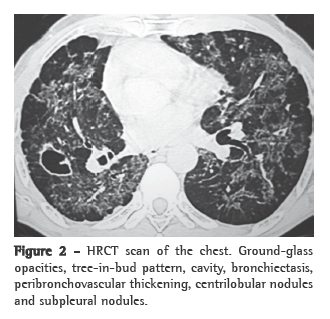

A HRCT scan (Figure 2) can reveal nodules, ground-glass opacities, tree-in-bud pattern, acinar lesions, parenchymal bands, peribronchovascular interstitial thickening, cavities, reticular pattern, "reversed halo" sign, scar-related emphysema and traction bronchiectasis.(8,9)